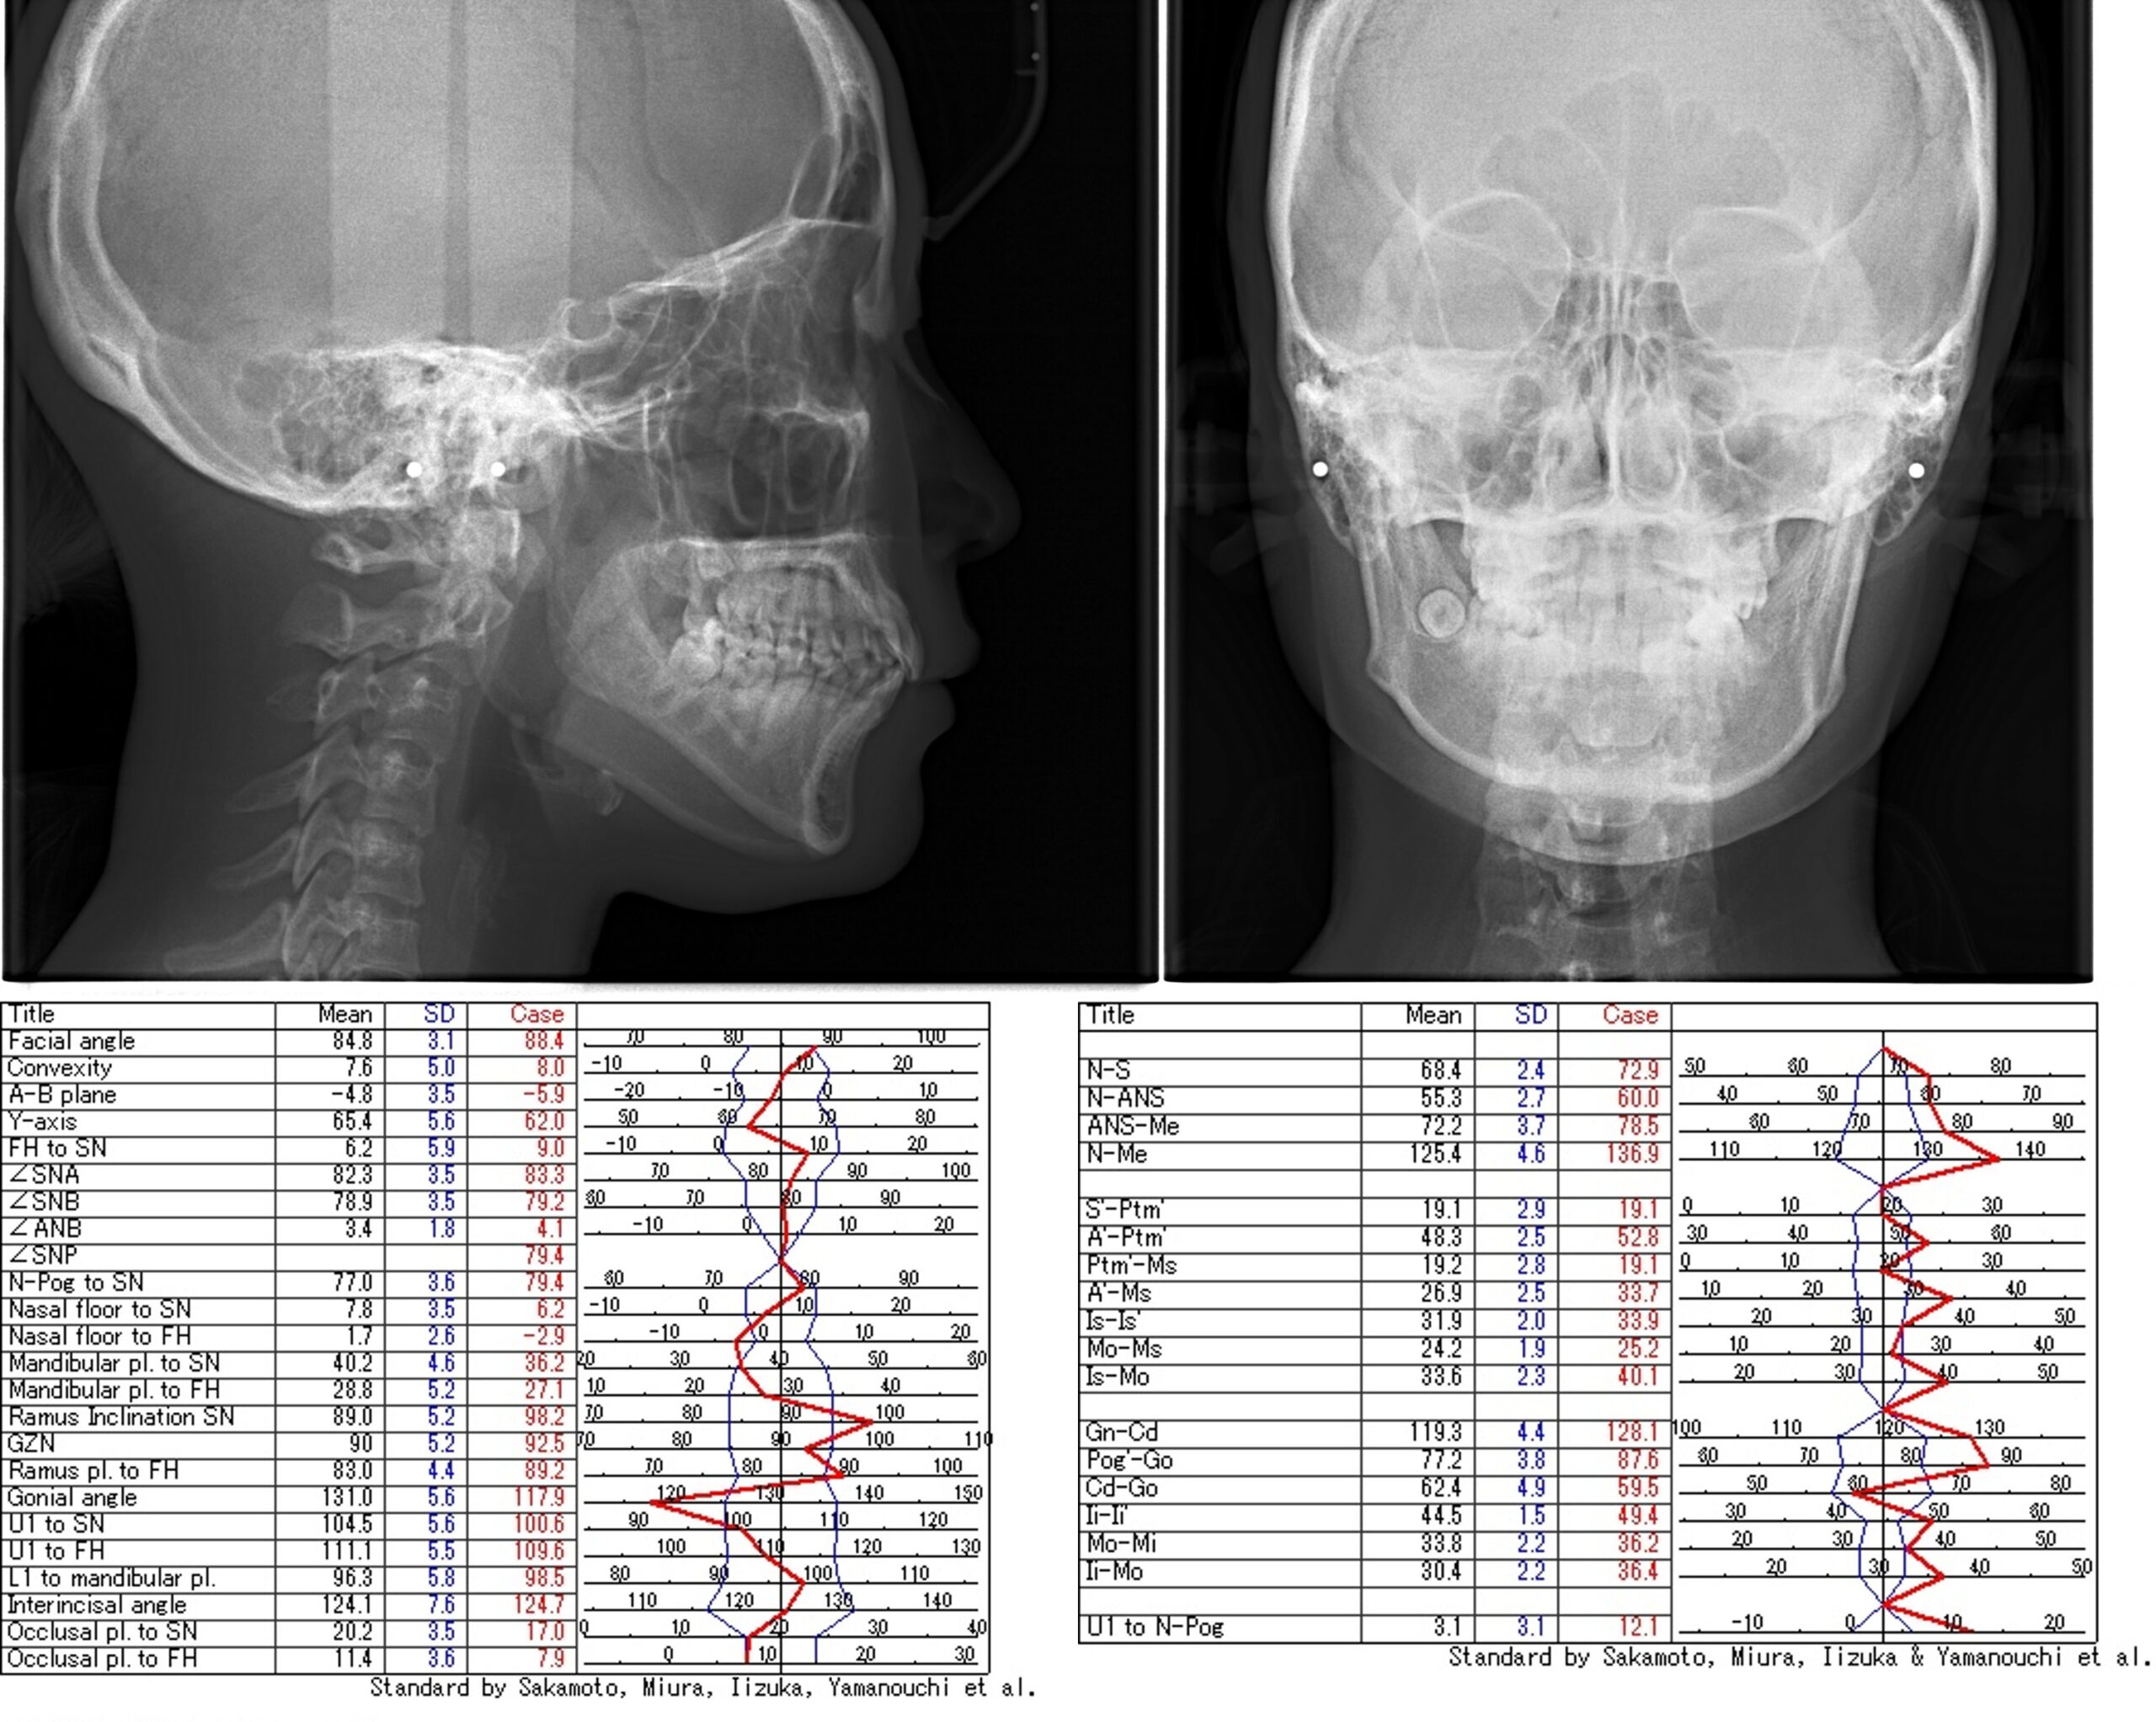

歯列矯正治療前の分析・診断

検査の際のレントゲン写真、お口の中の写真、お顔の写真をもとに分析・診断を行い、歯列矯正治療の計画を作成していきます。

オーダーメイド治療計画の作成(診断と治療計画および、治療期間)

最終的に自分の歯並びやかみ合わせがどう変化していくのかを歯列矯正治療を開始する前に動画にてご覧いただきます。お一人おひとりの骨格は異なり、歯並びやかみ合わせも千差万別です。このため、治療計画も当然のことながら一様ではありません。歯列矯正治療前の分析・診断を誤れば望ましくない結果を生み出してしまいます。